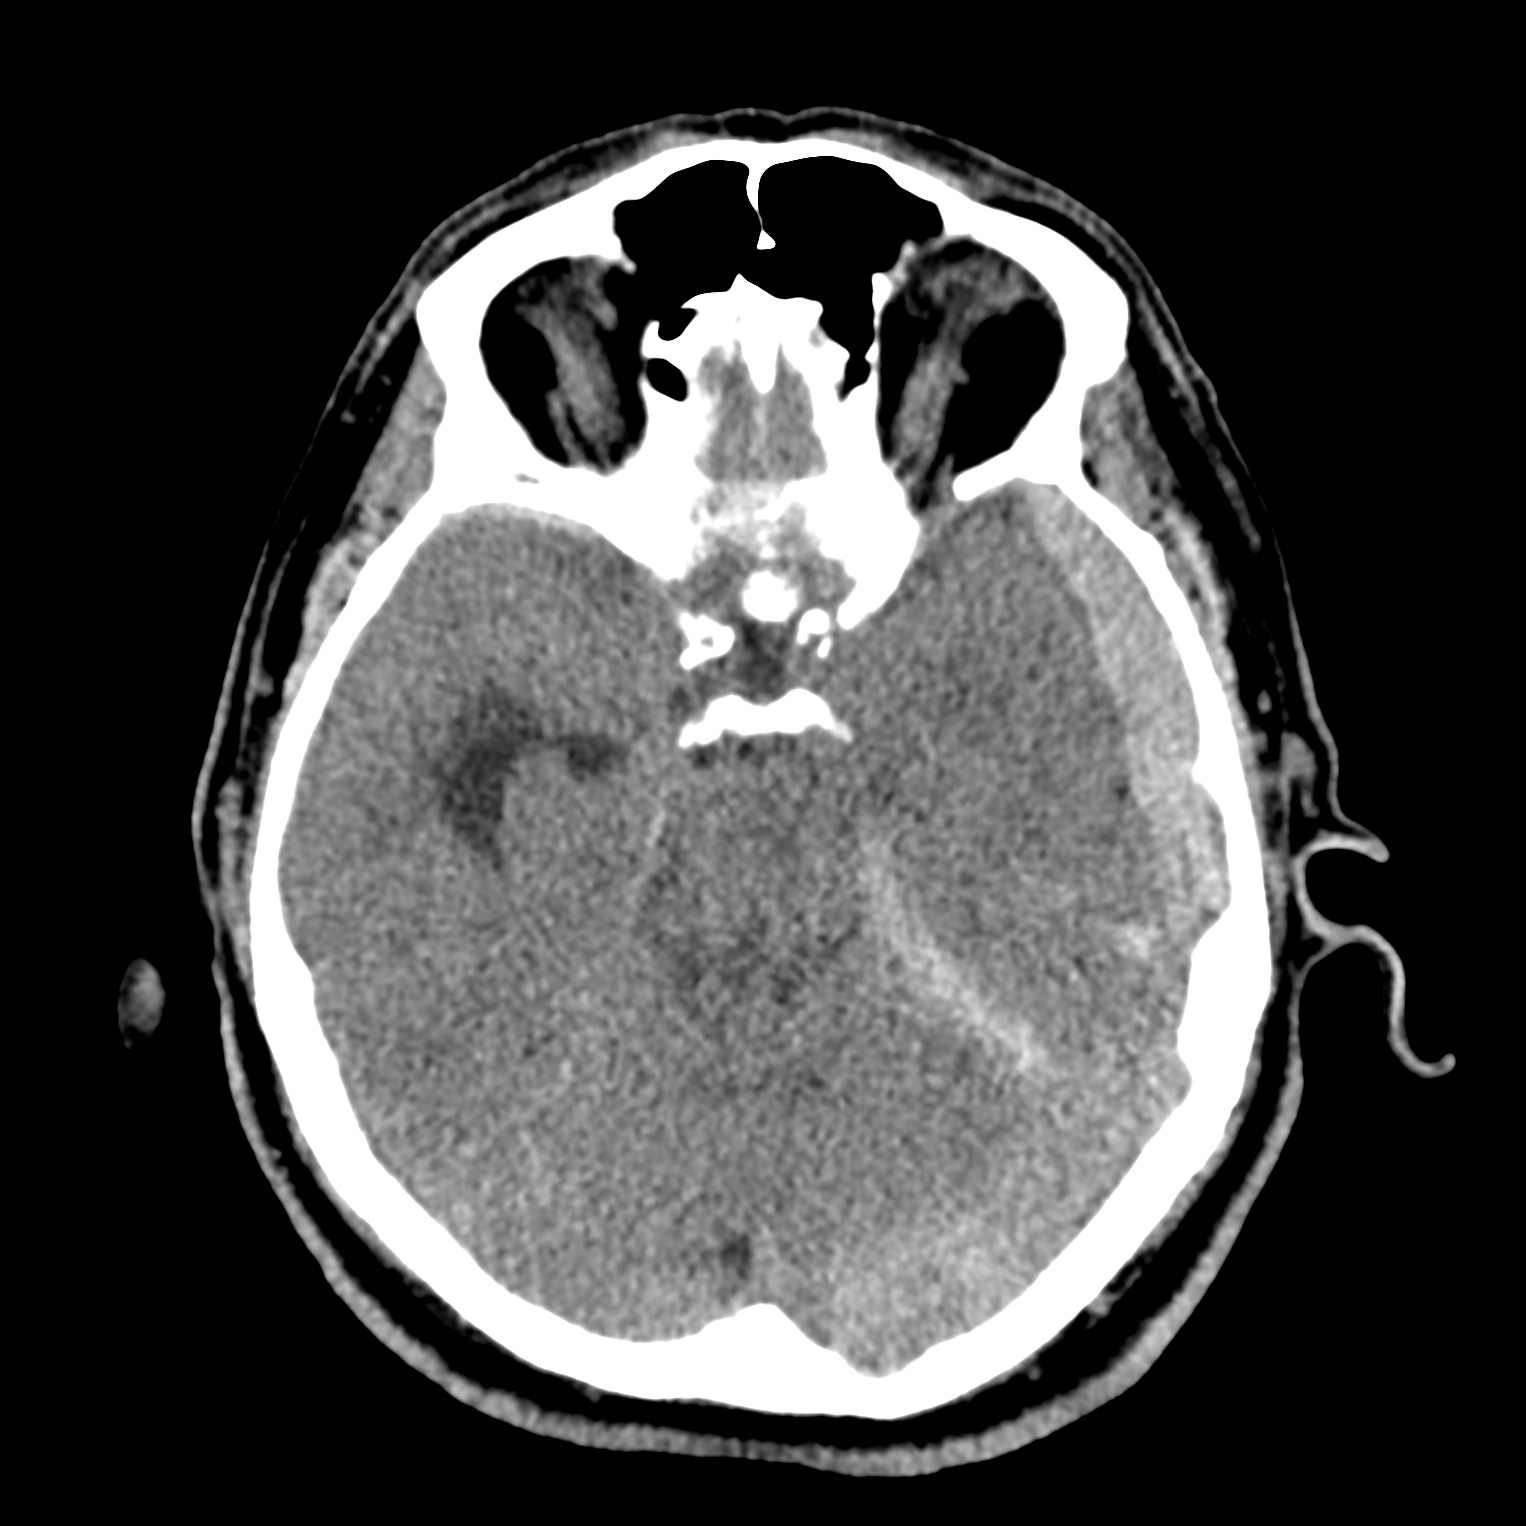

ちなみに画像診断とは、CTやMRIなどの画像を見て、正常か異常か、異常であればそれが何なのかを診断する仕事です。

Case courtesy of Andrew Dixon, Radiopaedia.org. From the case rID: 32383

医療従事者でなければ何のメリットも無いかもしれないのですが、実際の画像を自分でスクロールしながら学ぶことができるというのは、ものすごく大きなことだと思います。

さらに症例の解説を付け加えたら、読影能力アップのための強力なツールになるのではないかと期待しています。